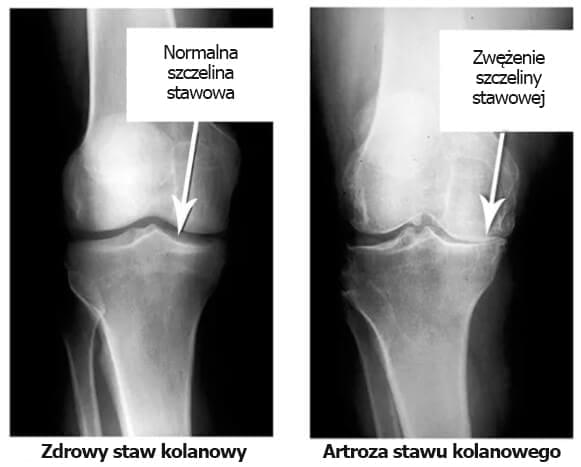

Proszę spojrzeć na te zdjęcia RTG, widać, że na prawym RTG nie ma jamy stawowej, kości ocierają się o siebie, powodując silny ból. Bardzo trudno jest zatrzymać ten proces!

Pani zdaniem, jak długo potrwa degradacja tkanek i stawu?”